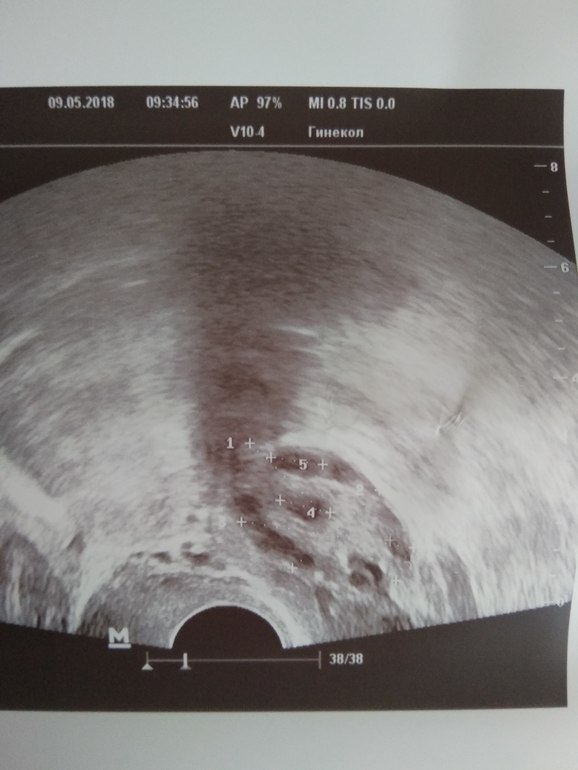

Правый яичник: строение фолликулярного аппарата по периферии, в одном скане до 40 фолликул размером 4-10 мм

Нормально ли, что в правом аж 40 фолликулов, а в левом всего 5? Вообще у меня всегда О только в левом, а вот в правом только в этом цикле первый раз почувствовала. И то это не О оказалась. Может ли влиять на овуляцию прием Кардиомагнила?((

Вот фото, посмотрите пожалуйста, визуально похоже на 40?(

Похоже на штук 10... Но это ж один срез...